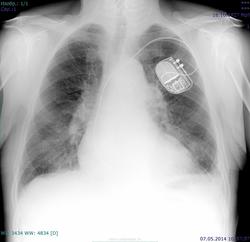

Пациент 1927 г.р, проф флг, архива нет, несколько лет назад перенес левостороннюю пневмонию. Похоже ли на саркоидоз (расширение корней, усиление рисунка, слева подчеркнута тень соска)?

А мне почему то кажется, что дела сердечные здесь.

Прежде всего , учитывая тень экс ( ивр) нужно исключать сердечную недостаточность.

Похоже на р-признаки застоя в малом круге кровобращения: расширение сердечной тени, расширение корней за счет сосудов, симптом "скачка калибра".

Сердечные дела.

Возможно, требуется подзарядка или замена ИВР. Если есть возможность - быстренько глянуть пульсацию на скопии.

А есть ли здесь признаки застоя?

Застой по мкк. Хотя левый желудочек почти не расширен, но корни расширены.